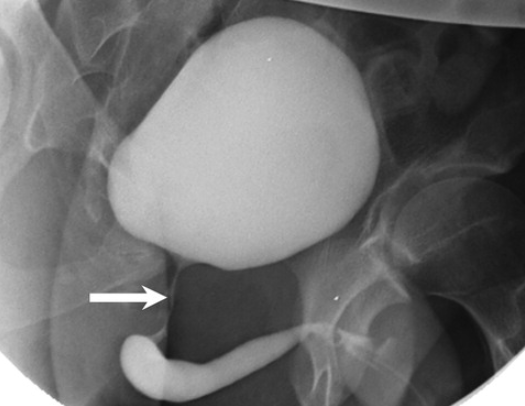

Goldman II